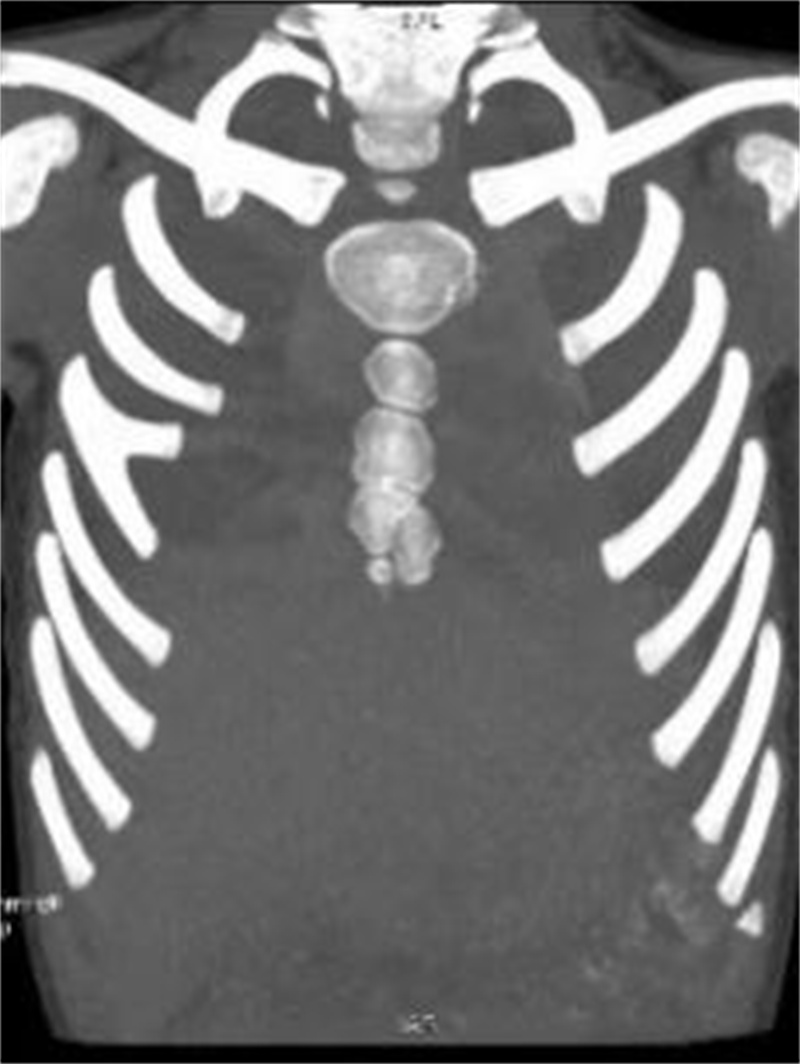

由于肋软骨在X线胸片上不显影,对于肋骨畸形的评价与确诊有局限性,目前多采用胸部 CT加肋骨重建检查。